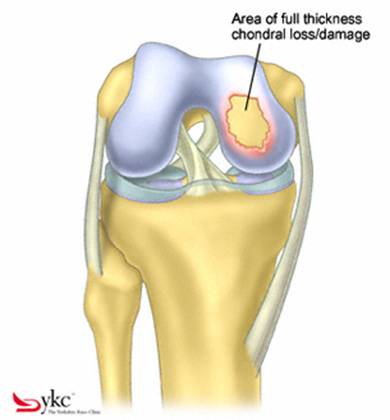

Chirurgul trebuie sa fie foarte atent atunci cand examineaza posteriorul condililor femurali. Daca se semnaleaza orice vatamare/rana/deteriorare pe suprafetele articulare, trebuie sa se cerceteze atent calitatea cartilagiului. Orice flapsuri instabile sunt inlaturate prin folosirea unui aparat de ras electric artroscopic sau curette. Apoi, un curette este folosit pentru a debrida stratul de cartilagiu calcifiat de la baza in toata grosimea defectului. Acest pas se bazeaza pe activitatea lui Frisbi, care a demonstrat vindecarea suprafetei articulare superioare la un cal, cand stratul cartilagiului calcifiat este indepartat. Cand indepartam stratul cartilagiului calcifiat, in general nu se foloseste un aparat de ras. Cu un aparat de ras este dificil de controlat cantitatea de os eliminat, si este posibil ca osul subcondral sa fie afectat.

Fig.21. Diagrama unei leziuni cartilaginoase.